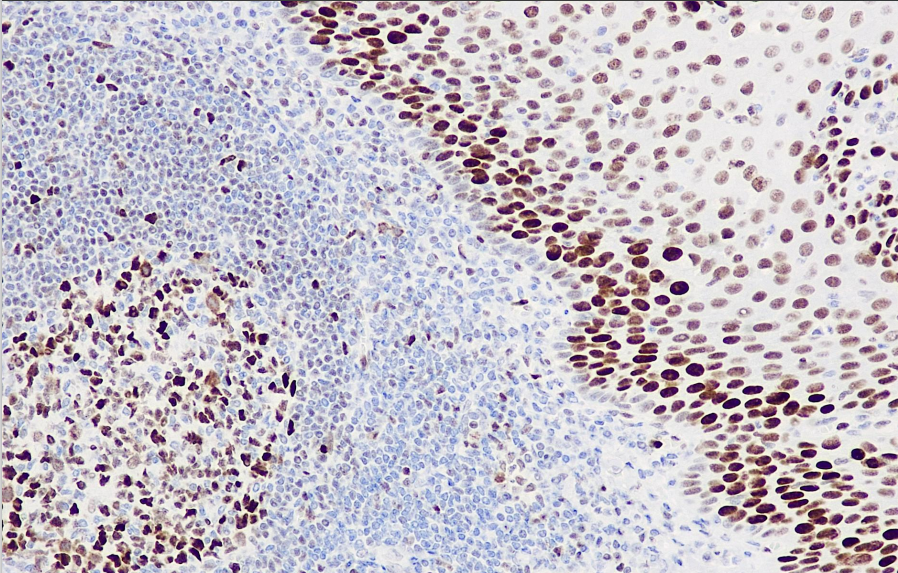

Cellular localization: nucleus

Positive control: tonsils

Rb is a tumor suppressor gene found in many types of cells that indirectly regulates cell growth. The absence or mutation of the Rb gene may be associated with the development of many malignant tumors. It is currently primarily used in research on malignant tumors such as esophageal cancer, gastric cancer, and bladder cancer.

Rb antibody reagents can specifically bind to Rb molecular antigens. Immunohistochemistry kits containing Rb antibody reagents are suitable for the auxiliary diagnosis of malignant tumors such as esophageal cancer, gastric cancer, and bladder cancer.